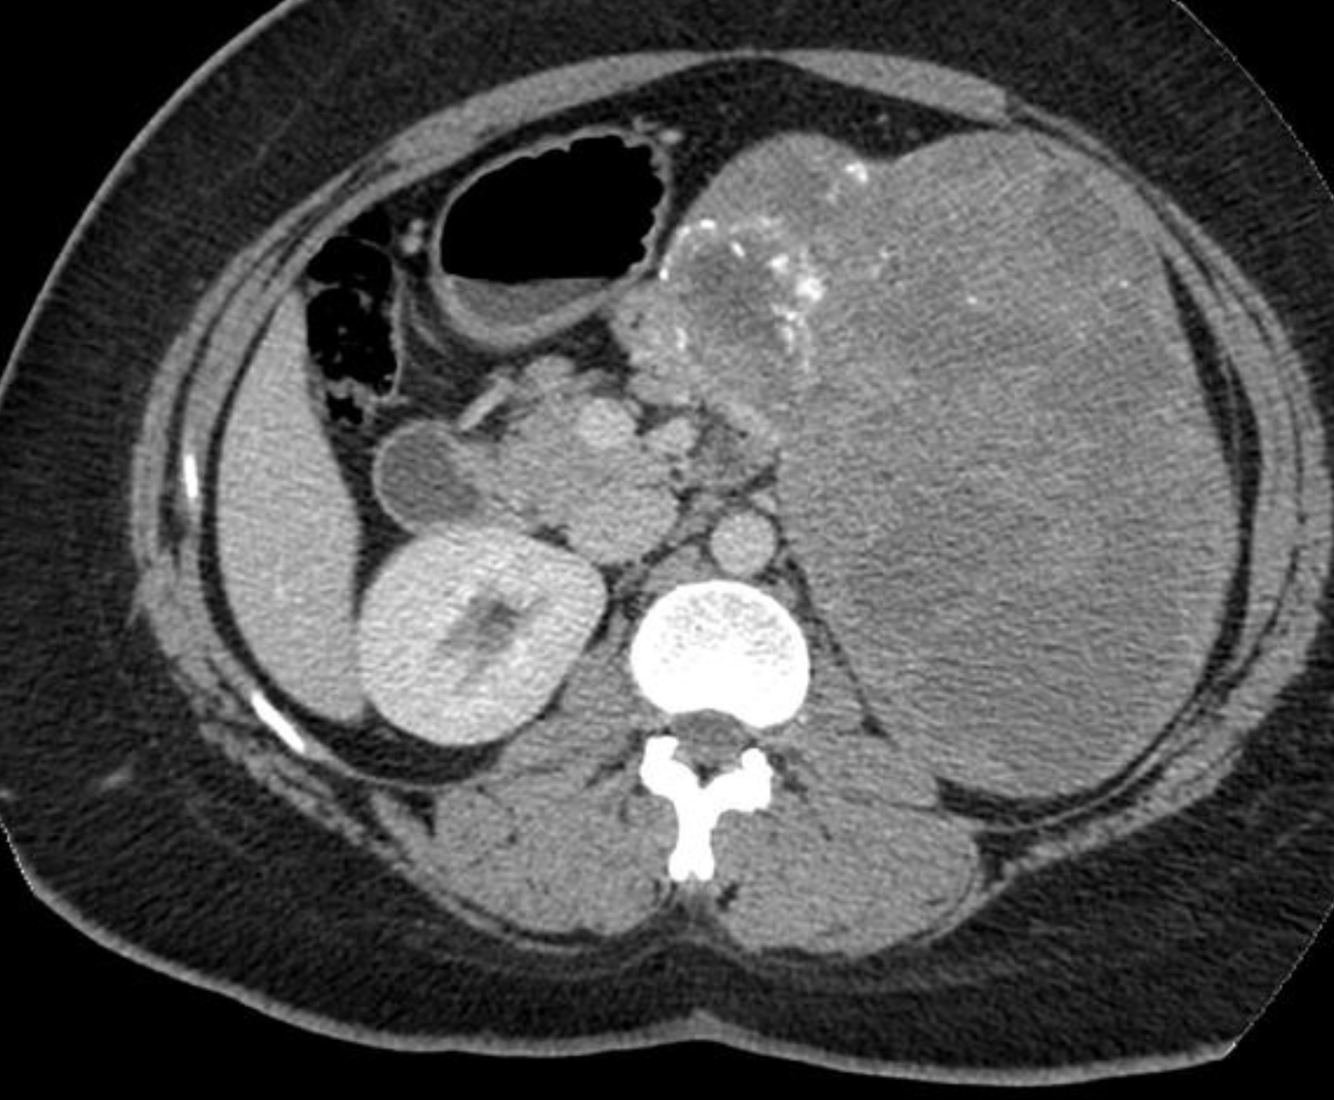

Case Discussion

Ultrasound-guided biopsy of the spleen was performed leading to the rare diagnosis of pancreas acinar cell carcinoma.

Pancreas acinar cell carcinoma highlights:

very rare <1%

exocrine tumour

larger size at diagnosis and often better prognosis than adenocarcinoma

some have paraneoplastic syndrome with hypersecretion of lipase (as in this case), which can lead to fat necrosis of subcutaneous nodules and polyarthralgia

On physical exam, this patient did have subcutaneous nodules in the lower extremities which would be clinically consistent with fat necrosis related to hyperlipasaemia.